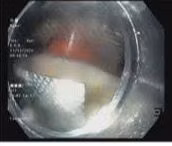

Tại khoa Thăm dò chức năng các bác sỹ đã thăm khám cho bệnh nhân qua nội soi ống tiêu hóa và phát hiện 1/3 trên thực quản gần cơ thắt trên có tổn thương dị vật dạng viên thuốc còn nguyên vỏ găm hai thành thực quản, phía trên dị vật ứ đọng nhiều dịch tiết và đờm rãi.

| Viên thuốc còn nguyên vỉ nằm trong thực quản bệnh nhân được camera nội soi phát hiện. Ảnh BVCC |

Các bác sĩ hội chẩn, đưa ra phương án lấy dị vật và đã gắp thành công dị vật sắc nhọn viên thuốc còn nguyên vỏ.